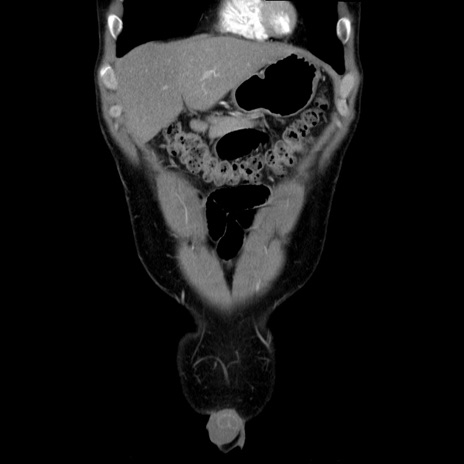

症例36(冠状断像)

【症例】20歳代 男性

【主訴】心窩部痛

【現病歴】今朝より上腹部痛あり。一旦軽快していたが再度出現したため救急要請。昨日夕に白身の魚を含む刺身を食べた。

【身体所見】BP 136/89mmHg、HR 74/min、BT 37.0℃、腹部:膨満、軟、心窩部に圧痛あり。反跳痛なし、筋性防御なし、腸雑音やや亢進あり。

【データ】WBC 17700、CRP 0.48